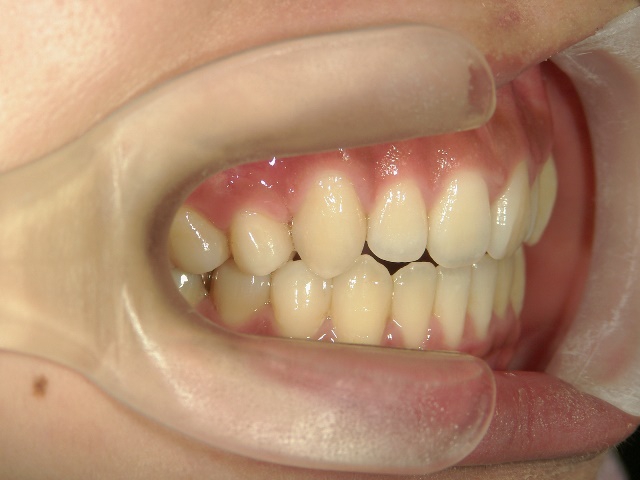

主訴:奥歯で噛んだときに前歯が噛み合わない

高校時代には、歯並びを改善しようと様々な矯正サイトを閲覧し、自分自身が開咬であることを知りました。開咬とは、上下の歯を噛み合わせた時に前歯に隙間ができることを言います。そういえば、麺を前歯で噛みきること、ハンバーガーにガブッと噛みつくことができませんでした。

2年を少し過ぎたころには歯並びが良くなり、開咬もだいぶ改善されました。結婚式を予定していたため早期終了をさせていただきましたが、開咬が治ってハンバーガーをガブッと噛みきることができるようになって、とっても嬉しいです。式でもきれいな歯並びで、思いっきり笑うことができました。